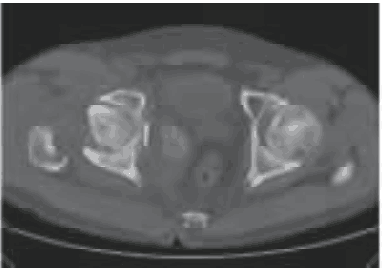

图2 术前CT示右侧髋臼骨折,股骨头向内脱位,关节内可见游离骨块

查体:跛行步态,全身无皮疹,右下肢短缩外旋畸形,右髋部轻度肿胀,局部无瘢痕、窦道,右腹股沟中点、大转子轻度压痛,右侧髋关节被动活动范围基本正常,右下肢肌力Ⅳ级,深感觉减弱,右下肢生理反射减弱、病理反射未引出。骨盆正位X线片及髋关节CT示右侧髋臼、股骨颈骨折,股骨头及髋臼内陷,关节内可见游离骨块(见图1~2);髋关节MRI示右髋关节及相邻盆底软组织渗出肿胀(见图3);骨扫描未见异常;颈椎、胸腰椎核磁示轻度退行性变。